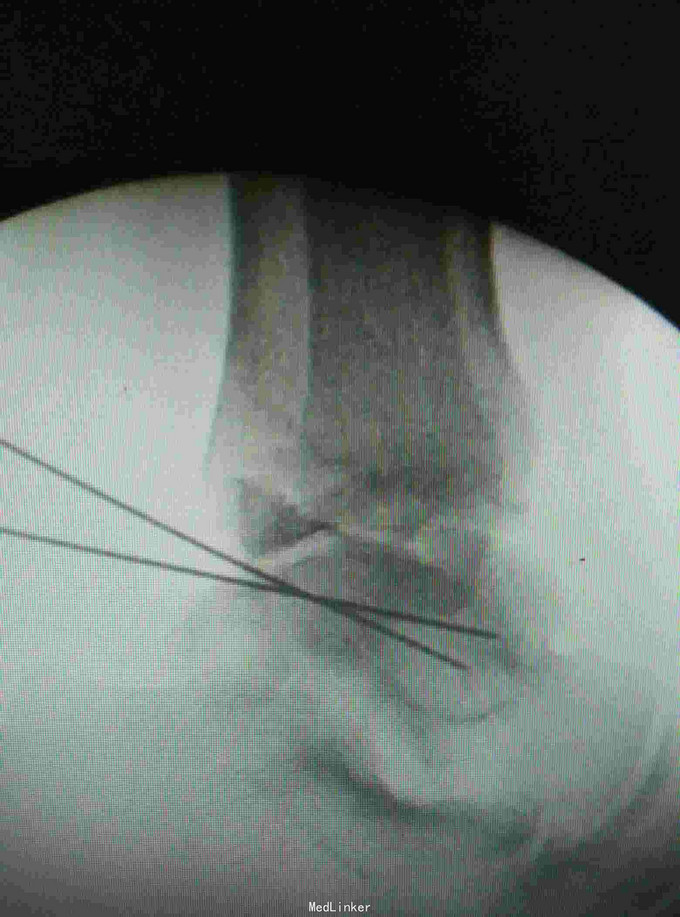

患者,男,45岁,车祸伤致右踝部肿痛,活动受限2小时入院

入院查体见局部肿胀,予完善影像学检查,

诊断是右距骨粉碎性骨折。给予行内踝截骨显露骨折端进行复位,采用Herbert钉进行固定。